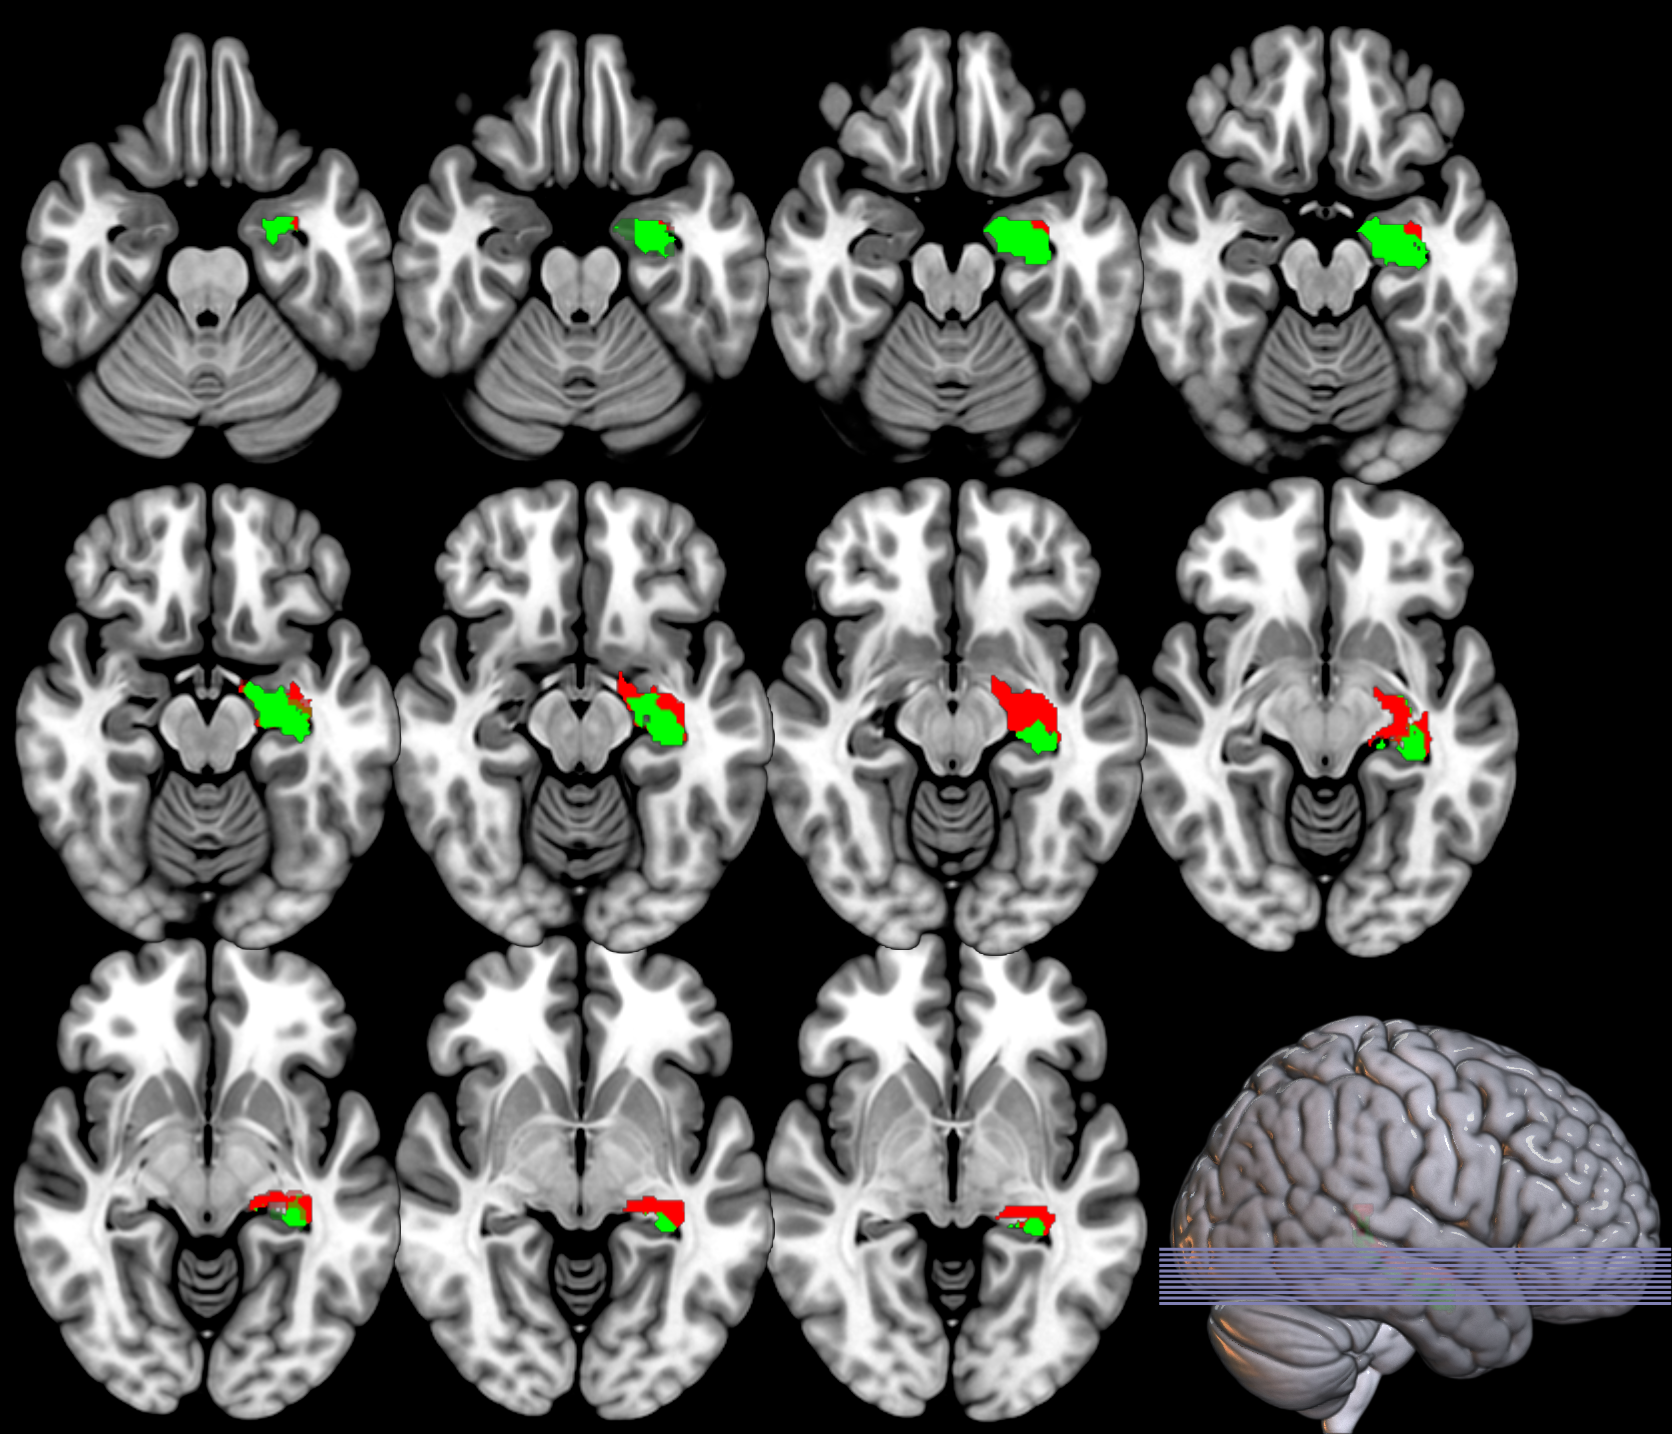

Based on the and values from the original dataset, and the ones obtained using a permutation analysis () for a selection of structures, e.g. hippocampus, we can compare the SPM with the previous inference approaches, as described in section 2.2.3. Note that in this paper the huge amount of voxels contained within an image limits the permutation analysis in this sense to some specific structures. Results on the hipocampus are depicted in figure 13. The permutation analysis reveals how the power of the approach is affected in this featured region, where a real effect might be found in almost the whole structure. The statistical power of the is preserved through the permutation procedure ( detected voxels vs voxels as shown in the same figure). It is also worth mentioning the CDF of the errors derived in the specific region and the distribution of the p-values within it. Recall that the dataset include advanced AD subjects thus the selected structure should be clearly affected by the disease.

To preliminary extend the analysis to the whole volume we approximately simulate the null distribution outside this featured region in two steps. First, we compute the set of p-values in the hippocampus (around voxels) following equation 16 and determine the T threshold that approximately provides the significance level, e.g. . Then, assuming that for any the probability of observation is , we threshold the rest of the image to obtain the significant voxels showing an effect. This approach clearly needs the multiple-comparison correction as several dependent or independent statistical tests are being performed simultaneously at the given significance level. Therefore, we decrease the significance level down to to avoid the presence of false positives in permutation analyses and then compare with SPM in the whole volume using the aforementioned configurations. In figure 13 we show the detection ability together with the control of type I error in the approach (map in red font). Note how the permutation test affects the detection ability of the classical CV approach (map in green font) and how the uncorrected voxelwise SPM approaches (in blue font ) tends to inflate false positives.